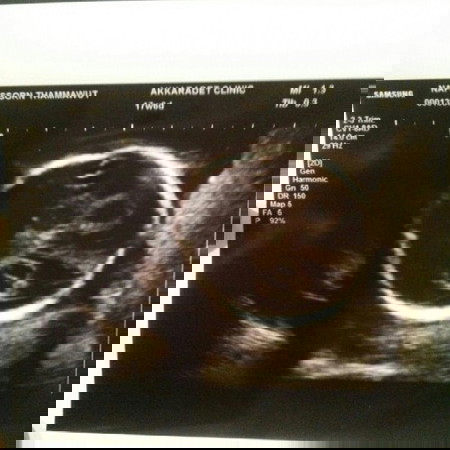

ตอนนี้ตั้งครรภ์ได้17วีค วันนี้หมอได้อัลตร้าซาวด์ ร่างกายปกติดีทุกอย่างแต่หมอได้ตรวจเจอถุงน้ำในสมองเด็ก อยากทราบว่าถุงน้ำในสมองนี้จะยุบหายไปประมาณกี่เดือนคะ มีคุณแม่ท่านไหนตรวจเจอแบบนี้บ้างคะ ตอนนี้เครียดมากเลยค่ะ